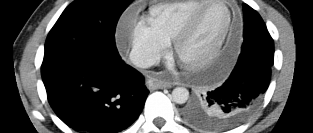

Сахарный диабет и скрининговая КТ-ангиография коронарных артерий. Обосновано ли использование?

Скрининг в отношении бессимптомного обструктивного атеросклероза коронарных артерий у пациентов с са...

15.12.2014 6426 #сахарный диабет #сахарный диабет 2 типа #КТ-ангиография